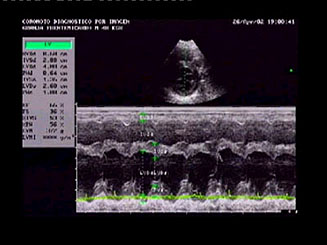

El movimiento paradójico del septo interventricular

secundario a la sobrecarga de volumen del ventrículo

derecho se observó claramente en el modo M, concretamente

en el corte transversal para-esternal derecho del ventrículo

izquierdo. Muchos de los corazones estudiados presentaban

derrame pericárdico, todos zonas hiper-ecogénicas

(compatibles con fibrosis) en el miocardio del septo

interventricular y alguno contraste ecográfico

espontáneo signo presuntivo de trombo-embolismo.

Con el Doppler color se detectaron turbulencias en

la arteria pulmonar y en las válvulas aurículo-ventriculares.